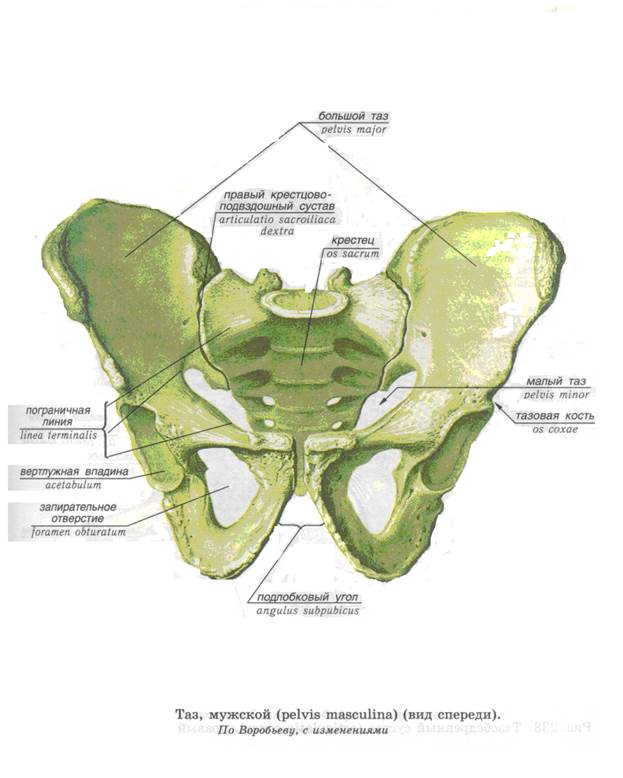

Анатомия малого таза: детальные схемы и изображения